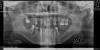

Leticia Опубликовано 19 января, 2010 Поделиться Опубликовано 19 января, 2010 Сразу оговорюсь,что прицельного снимка на руках нет.Завтра прием у терапевта Предыстория такова. В ноябре начато лечение 34 зуба. В плане - пломбировка каналов и пломба.Чистка каналов растянулась на несколько приемов, т.к каждый раз чувствую боль. С открытыми каналами хожу еще 2 недели в связи с перелетом в др страну. На месте в клинике один ортопед приговаривает к удалению, след. решает оставить - еще 2 недели открытые каналы. За всё это время боль была при касании инструментом во время очередного осмотра и при попадании пищи 18.01 - подготовка для дальнейшего протезирования. Прочистили и запломбировали каналы, временная пломба. Как только отходит анастезия - начинается ноющая боль. 19.01 добавляется боль при касании зуба довольно сильная. За неимением пока другого, ортопантомограмма ноябрьская Ссылка на комментарий